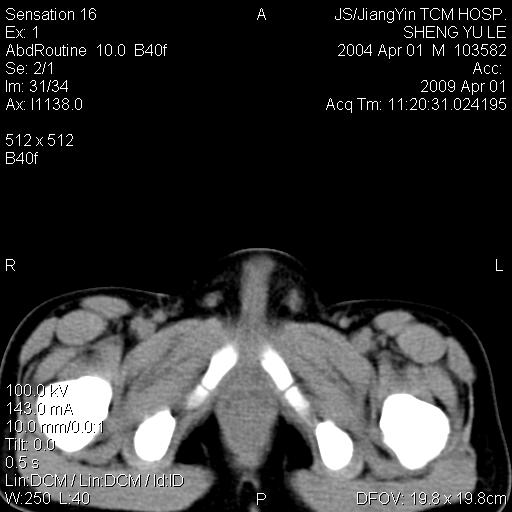

m,5岁。尿痛尿频数天。既往无病史。ct平扫腹盆腔积液。膀胱壁明显增厚。另可见心包增厚。wbc5万,骨髓穿等结果。请指教。

膀胱影像表现结合临床应该是急性膀胱炎症,但为什么有腹水呢?双肾输尿管无扩张,泌尿系压力应该不大不至于引起尿外渗,应该是腹膜感染引起的,但楼主没有提及相关症状,腹膜及膀胱结核?患者白细胞5万(结核不至于这么高啊),脾脏增大,是不是有白血病?进一步检查。。

腹水,膀胱壁增厚,wbc5万,结合临床,支持感染性疾病---感染性腹膜炎、腹水,急性膀胱炎,败血症。期待结果。